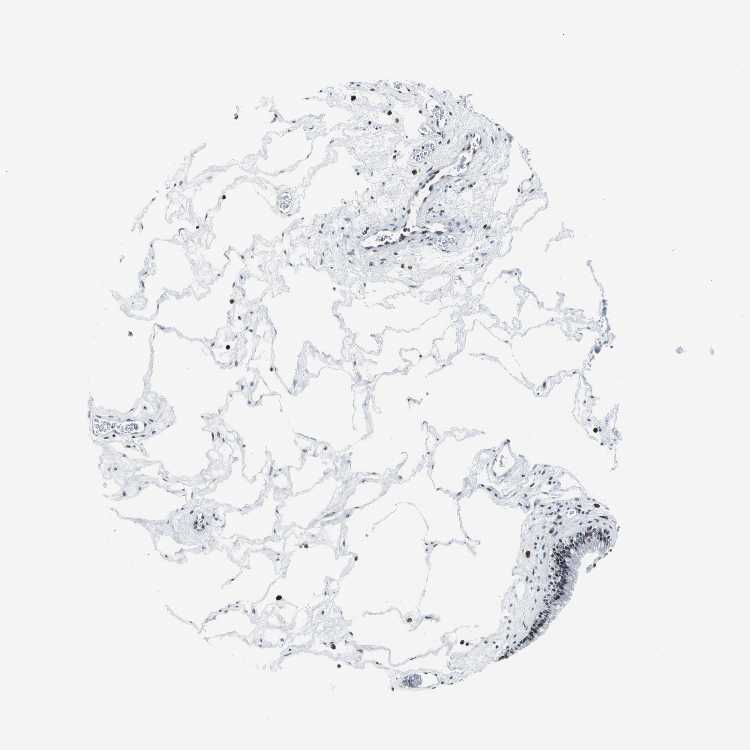

TISSUE PRIMARY DATA NASOPHARYNX Show tissue menu

NASOPHARYNX - Antibody stainingi

Antibody staining in the annotated cell types in the current human tissue is reported as not detected, low, medium, or high, based on conventional immunohistochemistry profiling in selected tissues. This score is based on the combination of the staining intensity and fraction of stained cells.

Each image is clickable and will lead to virtual microscopy that enables deeper exploration of all samples and also displays staining intensity scores, fraction scores and subcellular localization as well as patient and tissue information for each sample.

Antibody CAB004224

Respiratory epithelial cells Medium